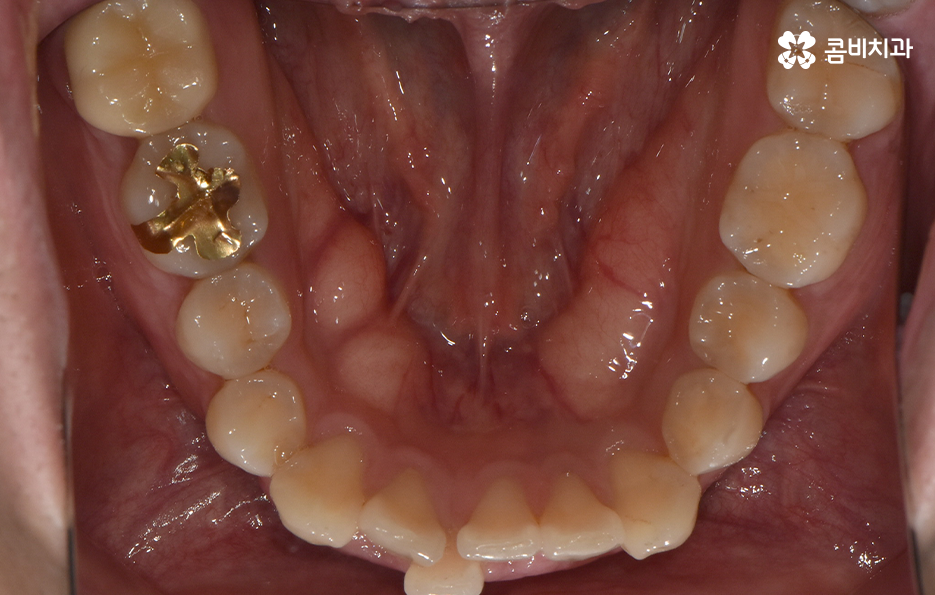

하지만 위에 보시는 환자분의 사례는 윗니와 아랫니의 교합을 고려하고 얼굴형, 골격 등을 고려했을 때도 아랫니만 교정이 가능했던 사례인데 일반적으로 윗니가 아랫니를 살짝 덮고 있어야 하는데 아랫니의 앞니 부분이 유독 안으로 들어와 있었기 때문에 아랫니교정 만으로도 치아교정이 가능했던 사례라고 보시면 좋을 거예요

위 환자분의 사례로 보면 아랫니 중에 하나가 유독 앞으로 튀어나와 있고 나머지 치아는 안으로 들어가 있기 때문에 교합으로 따져볼 때는 아랫니를 전체적으로 앞으로 이동시켜야 했기 때문에 비발치로도 충분히 교정이 가능했고 아랫니교정 만으로도 치료가 가능했어요